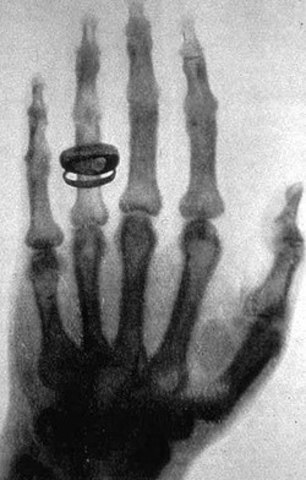

• rayos x

rayos x

es una radiación electromagnética, invisible para el ojo humano, capaz de atravesar cuerpos opacos y de imprimir las películas fotográficas. su inventor fue Wilhelm Conrad Röntgen